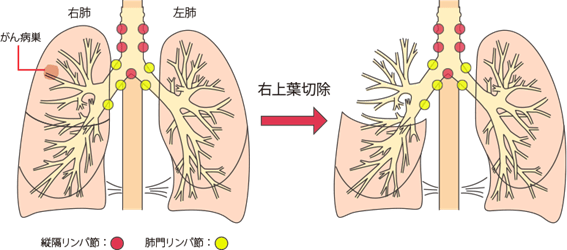

手術の範囲は?

標準的な手術:肺の房(肺葉)を切り離す

肺は右が三つ、左が二つの肺葉に分かれています。ぶどうの房が太いつるに右に三つ、左に二つぶら下がっているのを想像してください。それぞれの房には気管支と血管が入り込んでいます。

この房のうちどこかにがんが発生したとき、房を単位として切り離すのが標準的です。

一番多く行われているのが房の一つを切り離す「肺葉切除」。

右肺の場合は上葉と中葉、中葉と下葉という二つの房をあわせて切り離す2葉切除が行われることもあります。

がんが房の根元付近にまで食い込んでいると、右あるいは左の全部の房を取り除く必要がでてくることがあります。

片肺全摘出術です。

全摘出は手術後の肺活量の低下が大きく、身体への負担も大きいので、そうするべきかどうかの判断は慎重になります。

リンパ節の郭清:がん細胞を残さないためにリンパ節をとる

肺の房(肺葉)を切り取っただけではがん細胞を全て取りきれたかはわかりません。

がん細胞はリンパ節を好みますので、肺門部や縦隔にあるリンパ節にがん細胞が残っている可能性があるからです。

残った肺を少し脇にどけて肺門部と縦隔のリンパ節を取り除きます。

取り除いたリンパ節は病理検査にまわされて、がん細胞の有無が検査されます。

肺がんのステージ別にみると、非小細胞肺がんではⅠ(ⅠA・ⅠB)・Ⅱ(ⅡA・ⅡB)・ⅢA期の一部、小細胞肺がんではI-ⅡA期の患者さんが手術の対象となり、ステージによって手術法が異なります。

非小細胞肺がん

- ・IA期:肺葉切除術または肺葉の一部を切除する縮小手術をおこない、同時に、周囲のリンパ節を一緒に摘出するリンパ節郭清(かくせい)もおこないます。

- ・IB・Ⅱ(ⅡA・ⅡB)・ⅢA期の一部:肺葉切除術または片肺のすべてを切除する肺全摘術をおこない、同時に、周囲のリンパ節を一緒に摘出するリンパ節郭清もおこないます。